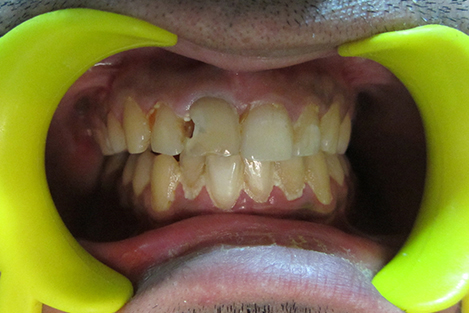

Vital Teeth Bleaching